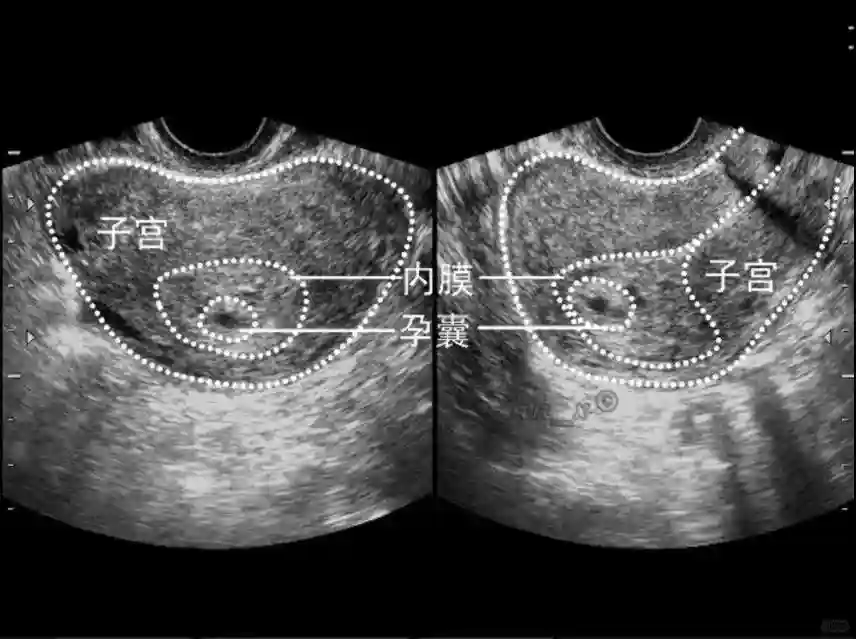

1??妊娠囊:早期妊娠囊:正常妊娠囊位于宮腔上段,表現(xiàn)為宮腔內(nèi)圓形或橢圓形的無(wú)回聲區(qū),周邊為完整的、厚度均勻的強(qiáng)回聲環(huán),強(qiáng)回聲環(huán)厚度≥2mm,強(qiáng)回聲是妊娠絨毛的回聲,隨著妊娠囊的增大,形成特征性的“雙環(huán)征” ,10周以后消失。正常的妊娠囊增長(zhǎng)速度是平均 1 mm /d。

5??羊膜:早孕期羊膜囊菲薄,超聲常不能顯示。孕7周以后加大增益或者用高頻超聲可以顯示羊膜。羊膜囊位于絨毛膜內(nèi),胚胎位于羊膜囊內(nèi)。隨著胚胎增長(zhǎng),羊水增多,羊膜囊增大,孕12-16周時(shí),羊膜與絨毛膜全部融合,胚外體腔消失。宮腔線(xiàn)一側(cè)內(nèi)膜內(nèi)一圓形增強(qiáng)回聲區(qū),中央有小囊狀液性暗區(qū),宮腔線(xiàn)局部突起變形,稱(chēng)蛻膜內(nèi)征,用于判斷早早孕。

5??羊膜:早孕期羊膜囊菲薄,超聲常不能顯示。孕7周以后加大增益或者用高頻超聲可以顯示羊膜。羊膜囊位于絨毛膜內(nèi),胚胎位于羊膜囊內(nèi)。隨著胚胎增長(zhǎng),羊水增多,羊膜囊增大,孕12-16周時(shí),羊膜與絨毛膜全部融合,胚外體腔消失。宮腔線(xiàn)一側(cè)內(nèi)膜內(nèi)一圓形增強(qiáng)回聲區(qū),中央有小囊狀液性暗區(qū),宮腔線(xiàn)局部突起變形,稱(chēng)蛻膜內(nèi)征,用于判斷早早孕。#超聲 #早孕檢查 #妊娠